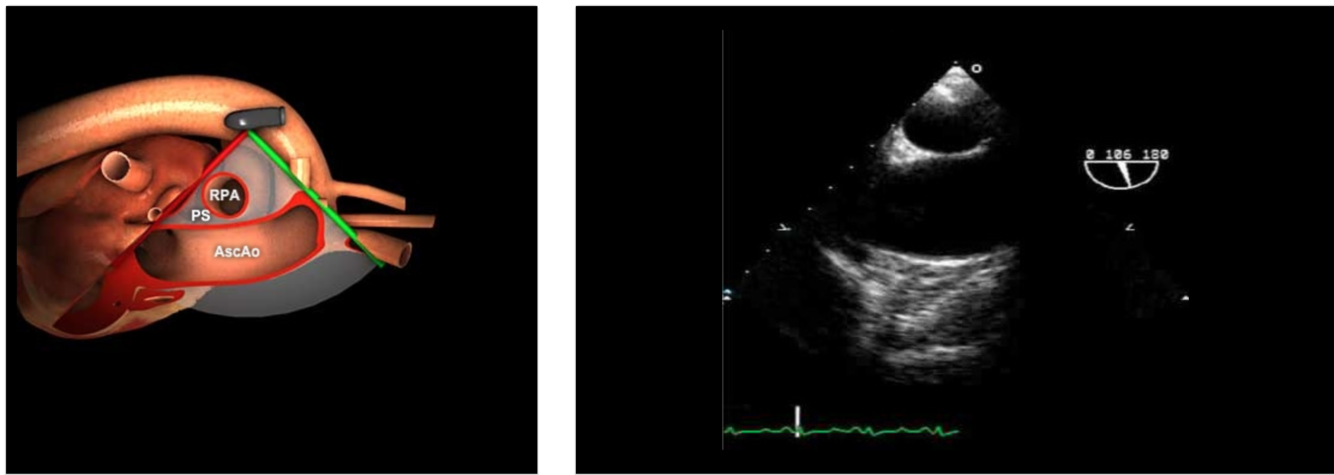

How do you get to a ME Ascending Aorta Long Axis view?

Insert the probe to the ME, sector depth 8-10cm, angle 0°

Find the ME AV LAX (120°)

Withdraw the probe to bring the right pulmonary artery in view

Decrease omniplane angle slightly by 10-20° to make the aortic wall symmetric